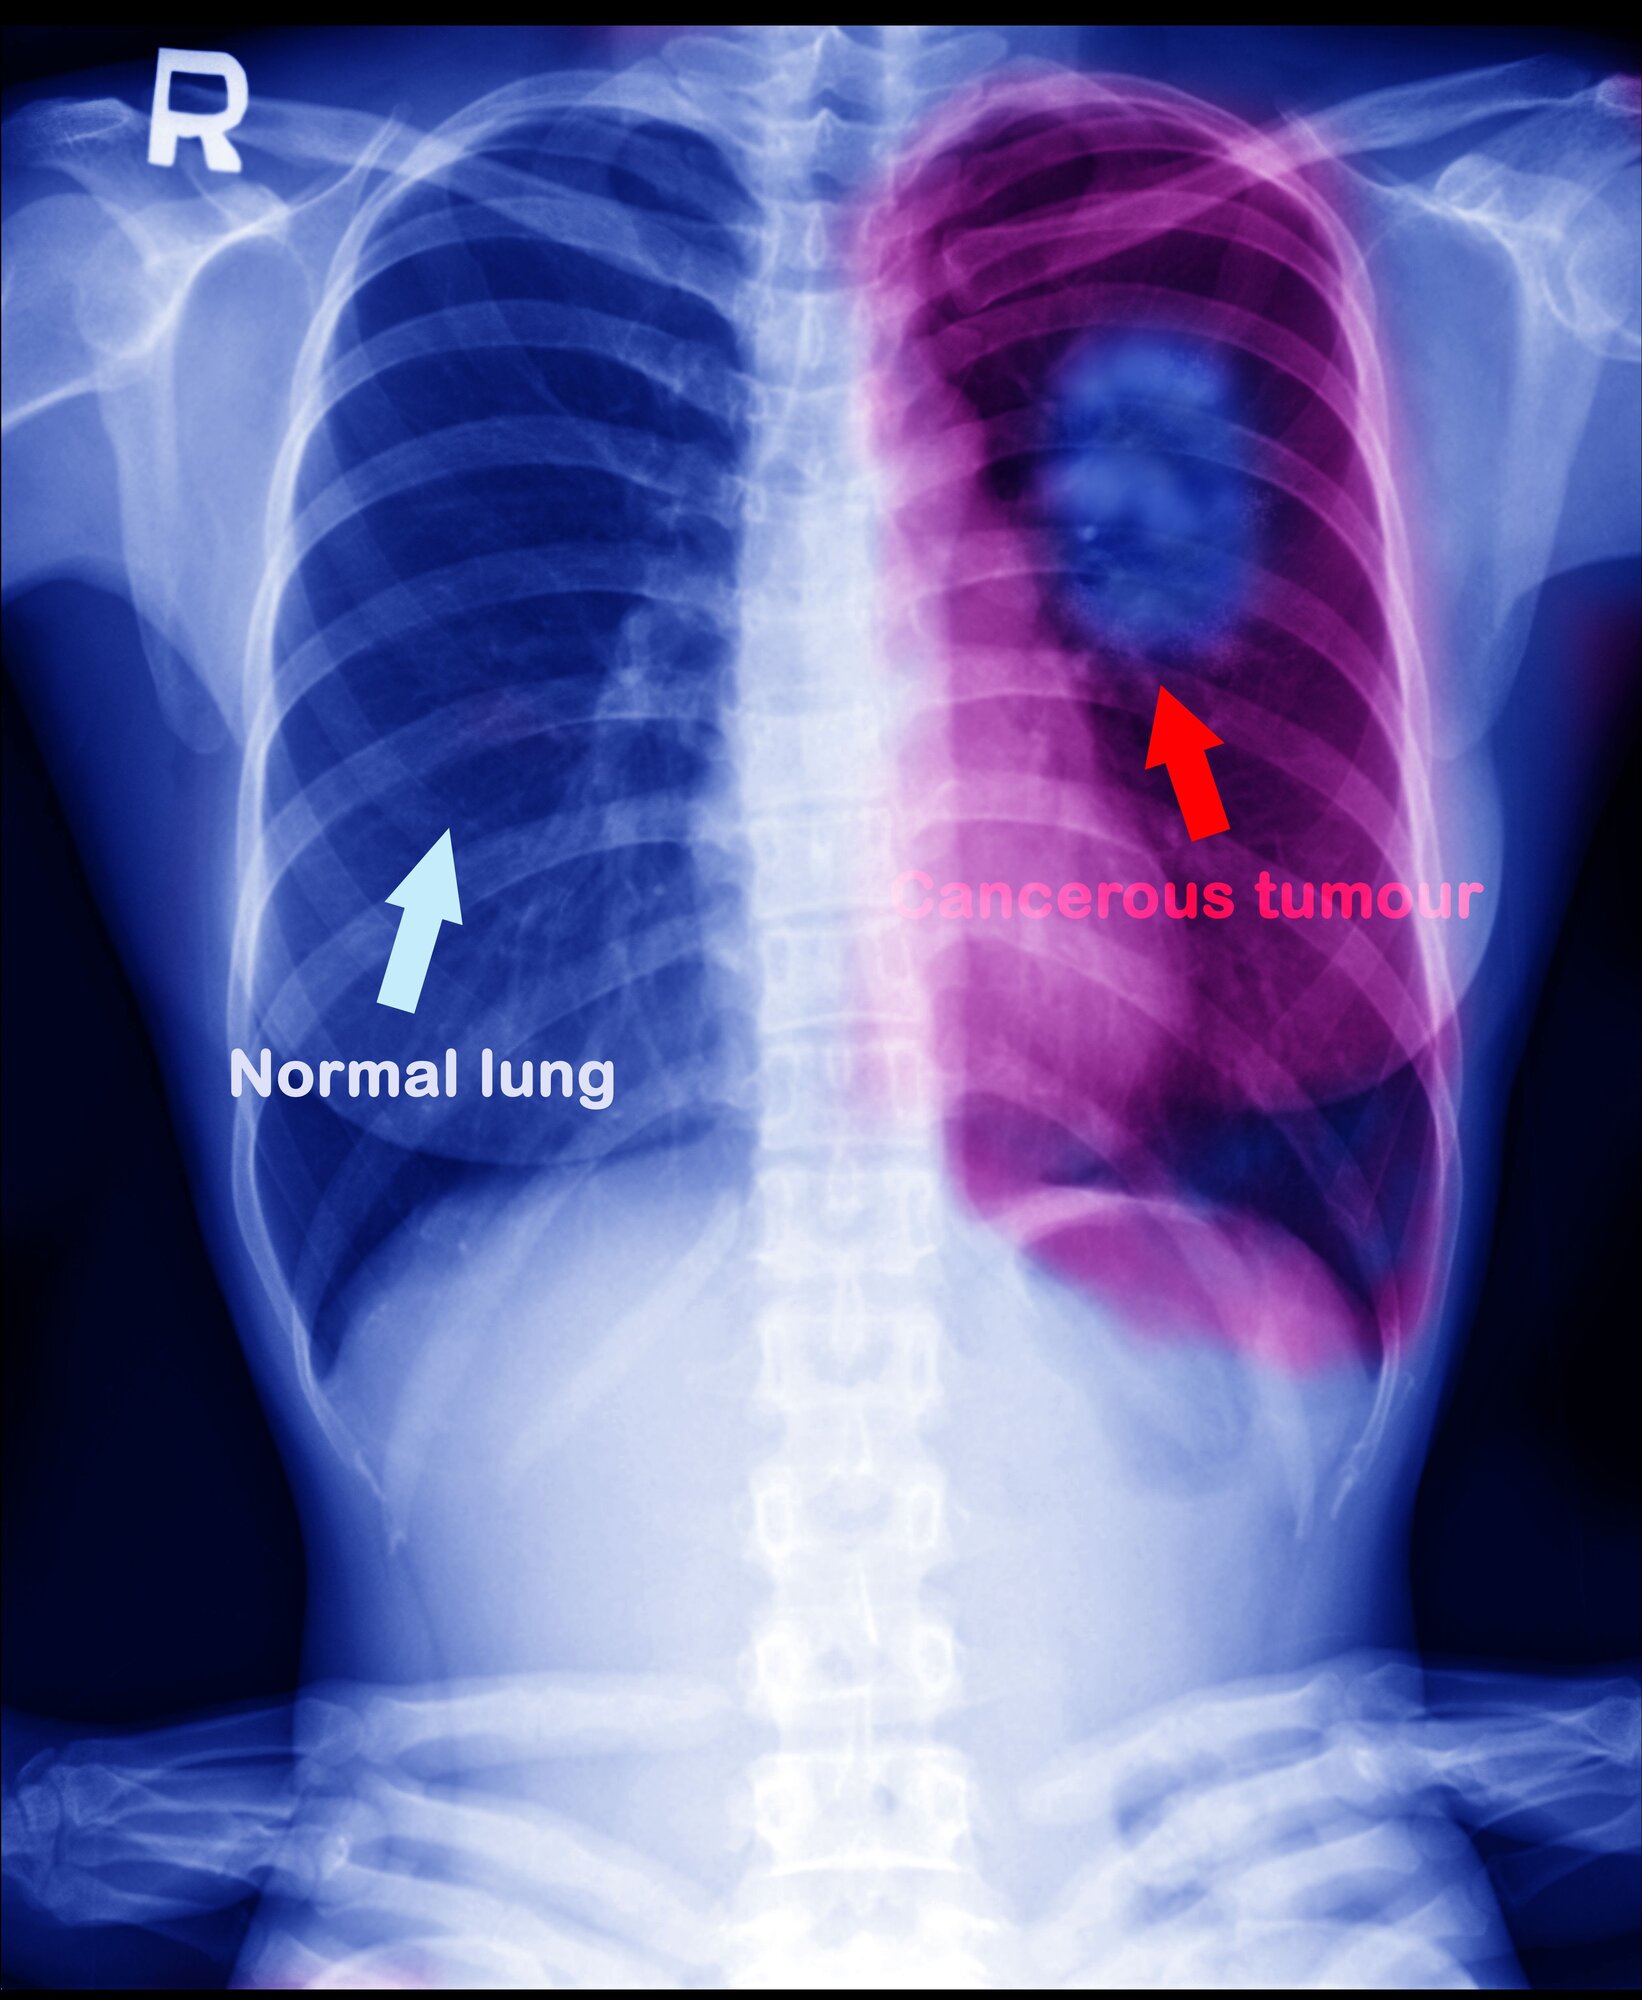

Lungekreft og føflekkreft er to kreftformer som immunterapi har svært god effekt på.